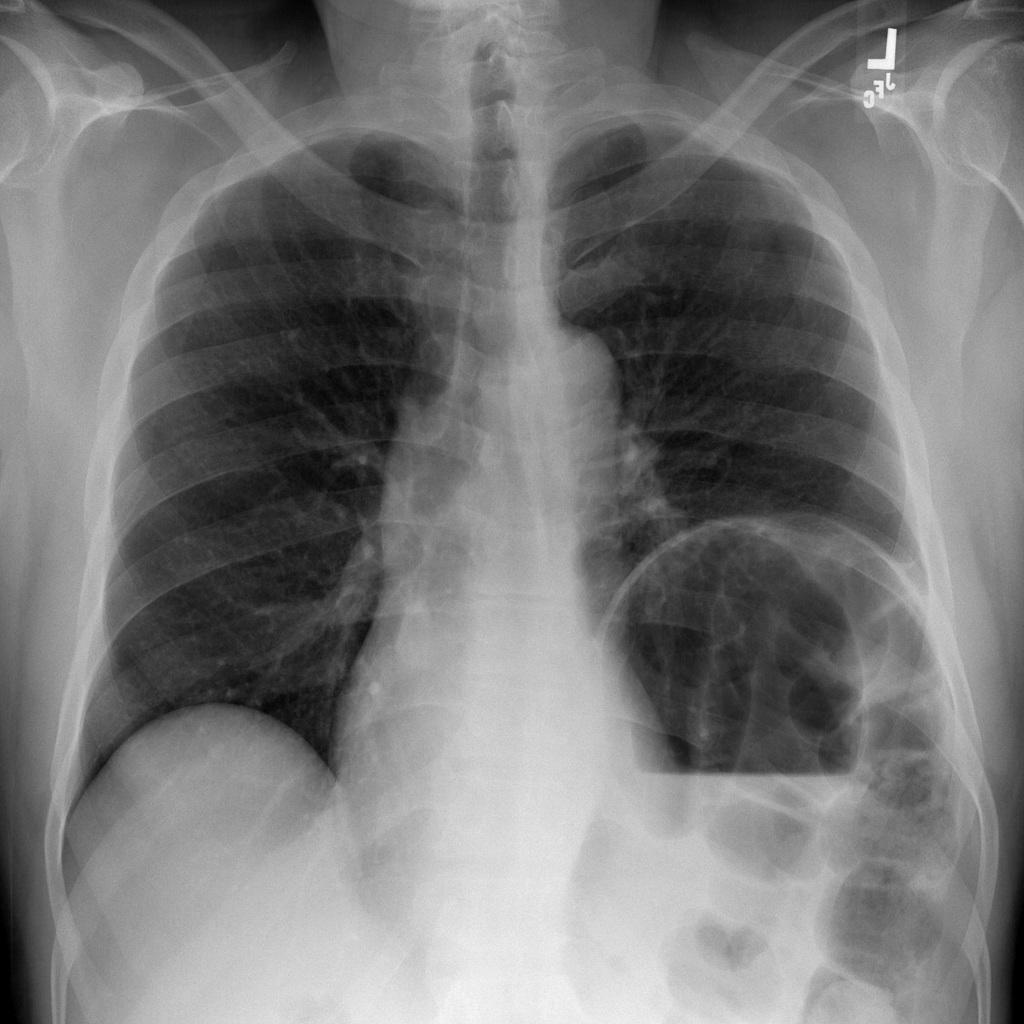

Showing up to 90 reference images for Hernia.

PAT-4F7E · IMG-000Hernia

PAT-4F7E · IMG-000

PA